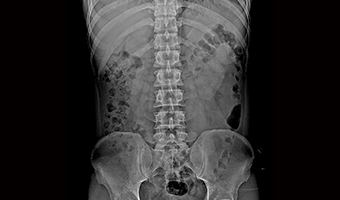

Uygulama Görüntüleri

Tam Boyut